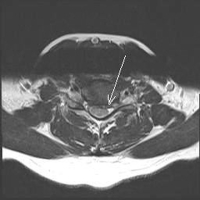

Using very small tools, the spurs are removed and the herniations are removed. A graft is then used to be placed in between the vertebral bodies to cause them to fuse together. The graft can be from your own bone (ICBG-iliac crest bone graft) or a PEEK cage which acts as a spacer and is filled with your own bone and demineralized bone matrix (DBM). The PEEK cage is imbedded with a thin film of titanium (see image) which is biologically active and allows bone to adhere to it. The discussion as to which graft to be used will be made before the anterior cervical decompression and fusion (ACDF) surgery is scheduled. Both grafts have advantages and disadvantages that will be discussed.

PEEK Cage